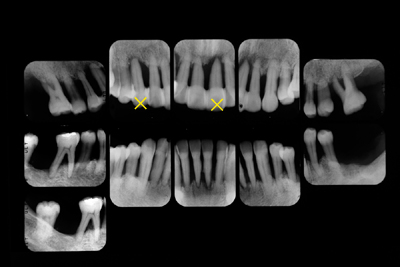

「歯周治療なく固定」は悪化

歯科医である息子さんの勧めで来院された60代男性、根尖まで骨吸収の重度歯周炎。

下はこれまでに何度もご紹介しているケースです。年齢重篤度ともとても似ています。異なることは、今回の症例は歯が動くからといって近医にてスーパーボンドで固定されたことです。左上1右上3は隣在歯にぶら下げられていますが保存不可能。

「歯の動揺がひどい(がどうしていいのか分からない),とりあえず隣とつなげて固定しておきましょう」は悪化させてしまい本当に困ります。